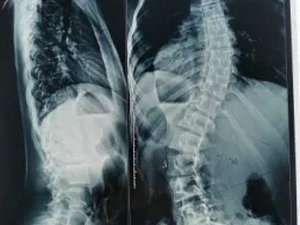

脊柱侧弯是指脊柱在冠状面、矢状面、水平面发生的三维骨骼畸形。X线诊断Cobb角超过10°,即可诊断为脊柱侧弯。患者会出现双肩不等高、腰或背部一侧隆起、对侧凹陷、胸廓畸形等外观改变,并会导致严重的身心健康问题。目前,脊柱侧弯已成为继肥胖症、近视之后我国儿童青少年健康的第三大“杀手”,防控形势严峻,主要表现在:

1.脊柱侧弯筛查需站立位全脊柱X光片正侧位。

2.骨盆前倾:矢状面 Cobb 角>50°。